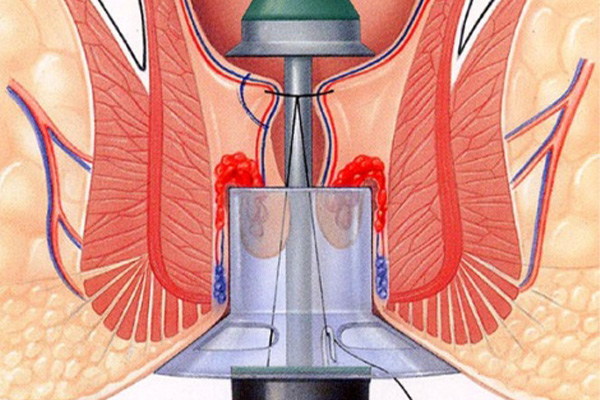

Dr. Jain specializes in the diagnosis and treatment of problems affecting the rectum, anus, and colon, including piles, fissures, and fistulas. He delivers compassionate and effective therapy.

For piles and circumcision available